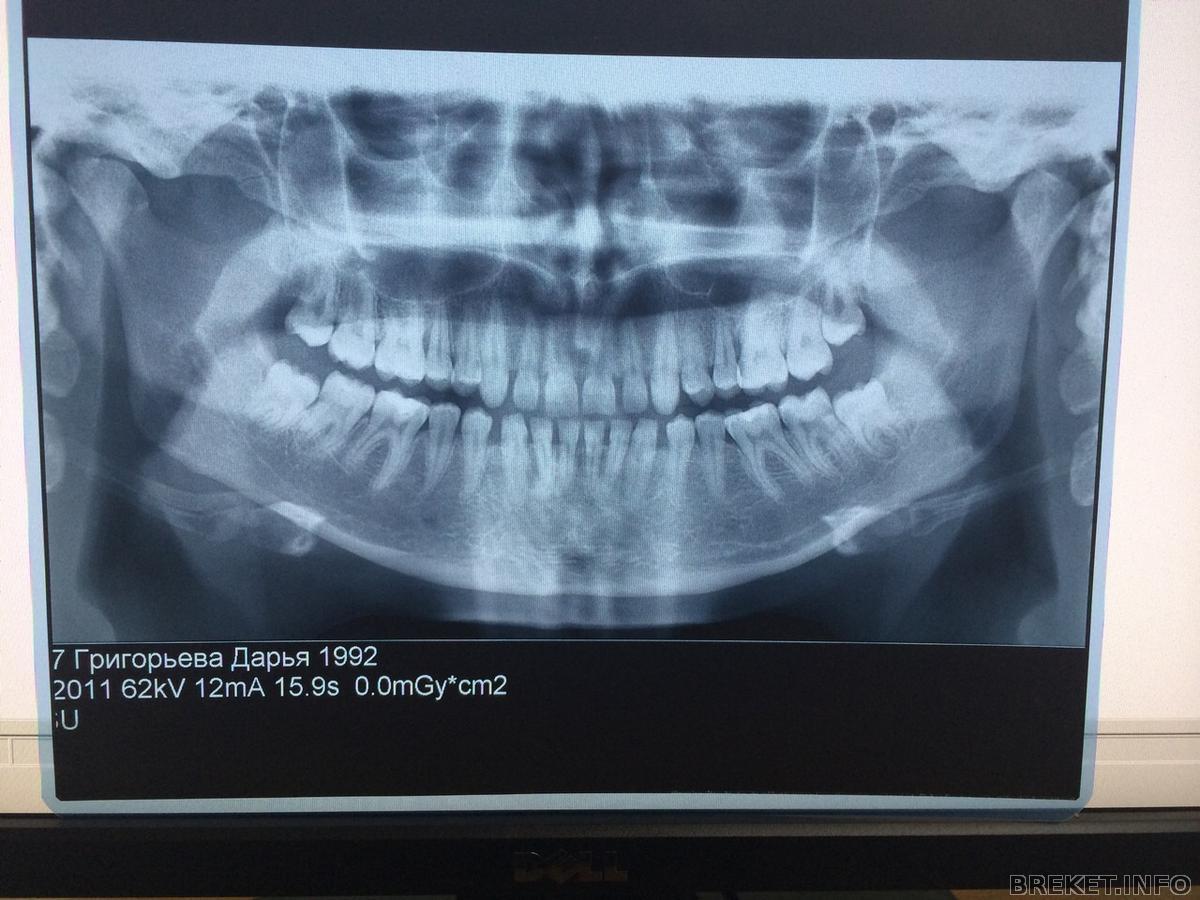

Меня зовут Дарья, мне 22 года, живу в Москве. Лет с 17 я решалась на брекеты и вот ура! это произошло, вчера налепили. У меня редкие зубки, то есть диастемы сплошь и рядом. Но при этом качество зубов, по версии не одного врача, отличное. Мучалась, думала, то говорили что разойдутся, то давайте лучше виниры, но я за сохранение своих зубов и за естественность. Два месяца занималась эстетикой перед установкой БС, вылечили 9! зубов, большинство с глубоким кариесом были, удалила все восьмерки, которые вылезли давно и корни их были ровные (тут мне просто повезло). Не скажу что я мучалась, я была готова ко всему, и по натуре терпеливый человек, так что и 4 пломбы за раз, и зубы мудрости мне удаляли по два, я даже была рада, что буду меньше есть) И вот сегодня, мой первый день с брекетами. Стоит керамика до клыков, пока только верхняя челюсть. Чувствую себя хорошо, совсем немного давит, хотя ночью задела случайно нижней челюстью и проснулась от дикой боли. Настрой боевой, и очень надеюсь на достижение прекрасной улыбки! Приложу пока только панорамный снимок, фотографии сделаю чуть позже.